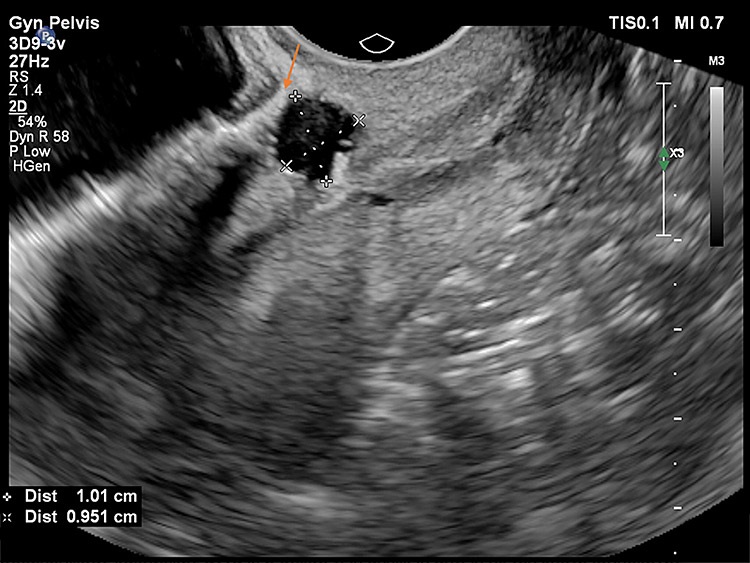

Στις παρακάτω εικόνες από ενδοκολπικό υπέρηχο φαίνονται παραδείγματα επιπέδου τρία προηγμένης τεχνολογίας υπερηχογραφικής μελέτης όπου σημαντικές λεπτομέρειες σε ό,τι αφορά τη θέση, το μέγεθος και την ανατομική συσχέτιση της Ισθμοκήλης, είναι εμφανή με καθαρό τρόπο, επιτρέποντας την εκτίμηση κατά πόσο μπορεί να γίνει χειρουργική επέμβαση ή όχι, και αν ναι με ποια τεχνική. Όλες οι εικόνες έχουν παραχθεί με υπερηχογραφική μηχανή Philips Elite, Costas Panayotidis operator.

Εικόνα 1 : Η ισθμοκήλη φαίνεται στο πάνω τμήμα της εικόνας που είναι μία κυστική μορφή όπου δείχνει το βέλος, γεμάτη με υγρό και φαίνεται ξεκάθαρα η ελαττωματική επούλωση.